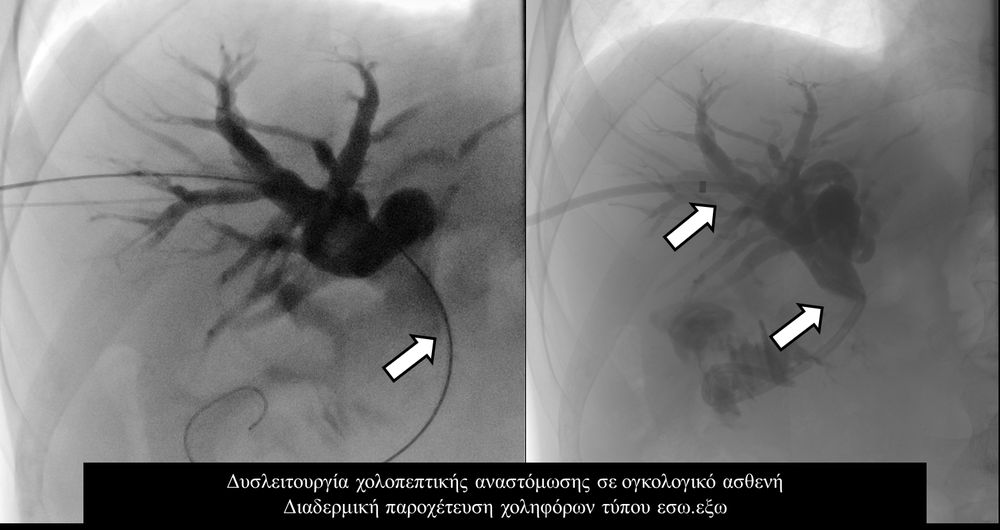

Η παροχέτευση των χοληφόρων σε αυτές τις περιπτώσεις θα πρέπει να γίνεται άμεσα, είτε ταυτόχρονα προς τα έξω και προς το 12κτυλο (έσω-έξω παροχέτευση), είτε μόνο προς τα έξω με τη βοήθεια pigtailκαθετήρα (εξωτερική παροχέτευση)

Η προσπέλαση σε όλες τις περιπτώσεις γίνεται διαδερμικά και η νοσηλεία του ασθενούς διαρκεί συνήθως μία ημέρα και ο ασθενής επιστρέφει στο σπίτι του την επομένη.